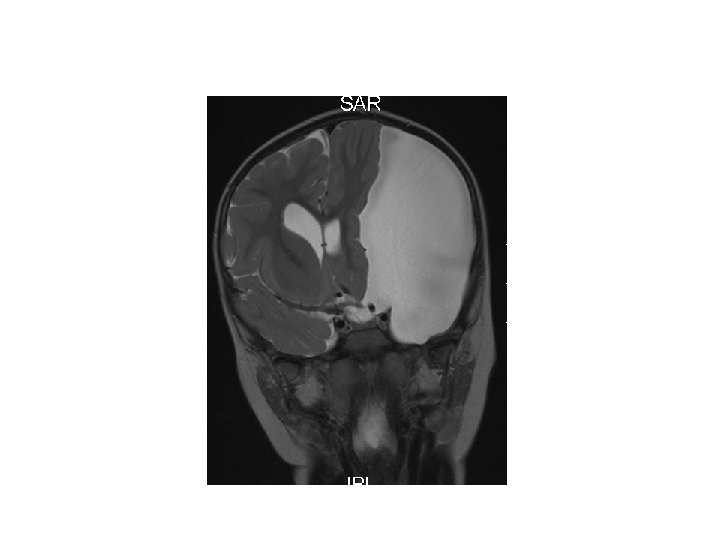

Greining • CT • MRI • Ísótóparannsóknir • Einkennalaust: Greinist oft fyrir tilviljun með CT eða MRI • Einkenni: Gullstandard MRI

Heilaskúmsbelgir - Arachnoid cysts • Skilgreining: – Heila- og mænuvökvafylltir belgir, þaktir heilaskúmsfrumum og kollageni, sem geta myndast á yfirborði heilans, innan heilans eða í mænunni.

Einkenni • Flestir einkennalausir • Breytileg eftir stærð og staðsetningu – – – – – Aflögun á höfði eða aukið höfuðummál Hydrocephalus Aukinn intracranial þrýstingur Höfuðverkur Þroskafrávik Krampar Hegðunarbreytingar Hemiparesa Ataxia O. fl.